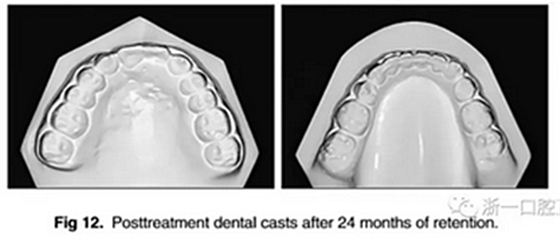

經(jīng)過24個月的保持后,咬合保持得很好(圖11 ; 圖12)。在上牙弓中,應(yīng)用固定舌側(cè)保持器以防止任何復(fù)發(fā)傾向。在下牙弓中,治療后拔除第三磨牙。